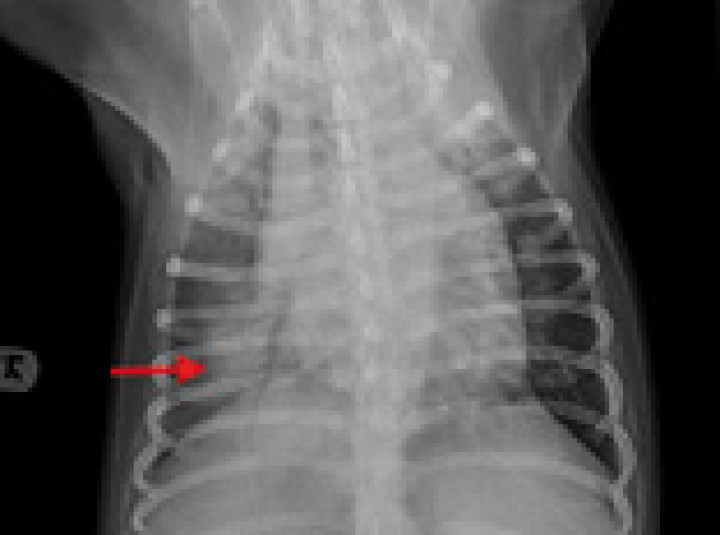

- Al igual que en la enfermedad degenerativa de la válvula mitral, la utilización de una fluidoterapia agresiva estaría contraindicada. Velocidades de cristaloides de 2-3 ml/kg/h deberían ser bien toleradas, pudiendo modificar estos valores según las pérdidas quirúrgicas o fallo cardiaco congestivo claro (Fig. 7).

<p>Radiografía dorsoventral de tórax de un perro con fallo cardiaco congestivo secundario a una cardiomiopatía dilatada. Se observa cardiomegalia y patrón alveolar en el lóbulo caudal derecho compatible con edema pulmonar de origen cardiogénico (flecha roja).</p>

Figura 7

Radiografía dorsoventral de tórax de un perro con fallo cardiaco congestivo secundario a una cardiomiopatía dilatada. Se observa cardiomegalia y patrón alveolar en el lóbulo caudal derecho compatible con edema pulmonar de origen cardiogénico (flecha roja).